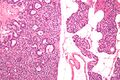

صورة مجهرية لغدوم الجار درقية (يسار) وغدة جارات درقية طبيعية (يمين). صبغة الهيماتوكسيلين واليوزين.